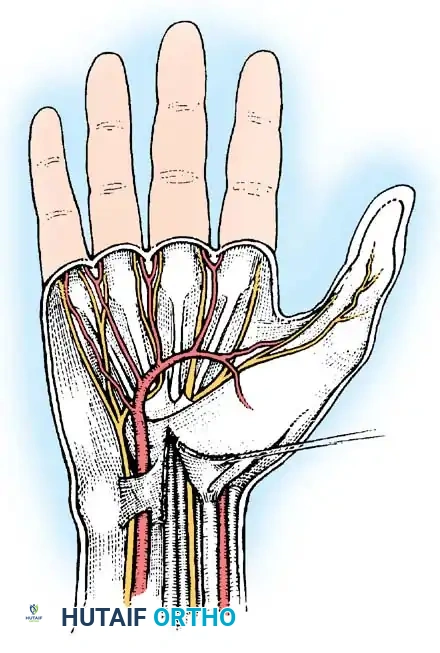

Step 4: Deep Exploration and Decompression

Once the TCL is fully divided, the median nerve is inspected for areas of pseudoneuroma (proximal swelling) or hourglass constriction. The recurrent motor branch is identified to ensure it has not been inadvertently injured or tethered by a transligamentous course.

Figure 13: Deep exposure demonstrating the decompressed median nerve. The recurrent motor branch is visualized and protected.

Figure 14: Anatomical variations of the recurrent motor branch of the median nerve (Lanz classification), highlighting the importance of careful distal dissection.

The distal extent of the release is confirmed by visualizing the superficial palmar arch and the fat pad indicating the distal edge of the flexor retinaculum. Proximally, the deep antebrachial fascia is released for 2-3 cm proximal to the wrist crease under direct vision.

- Nerve Injury:

- PCBMN Injury: Results in painful neuromas and numbness over the thenar eminence. Prevented by keeping the incision ulnar to the palmaris longus axis.

- Recurrent Motor Branch Injury: Results in catastrophic loss of thumb opposition. Prevented by releasing the TCL on its extreme ulnar border.

- Digital Nerve Injury: The common digital nerve to the 3rd web space is at risk during blind distal dissection.

Figure 22: Anatomical diagram emphasizing the "safe zones" for incision and dissection to prevent iatrogenic injury to the median nerve branches and superficial palmar arch.